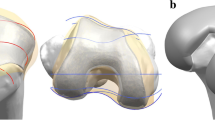

The patient-specific TKA is designed using an existing three-dimensional (3D) knee joint model [19, 20]. A patient’s bone is fundamentally used for the patient-specific geometry in the femoral component. The three patient-specific J-curves and the medial and lateral condyles from the patients’ normal articular anatomy are developed using computer-aided design (CAD) software in this study [17, 21,22,23,24,25]. A sagittal plane is introduced in the condyles, in which the anatomy of the articulating surfaces is extracted from the curves. Generally, the femur of a patient in the coronal plane provides asymmetric lateral and medial condyles that are defined as the coronal offset. The aforementioned patient-specific differences are considered in the patient-specific femoral component design (Fig. 1). The coronal offset is defined as the difference in height between the medial and lateral femoral condyles in the coronal plane [17, 26]. It typically supports an asymmetric extension gap between the tibial articular surface and the posterior femoral condyles. The lateral posterior condyle is shorter than the medial condyle and leads to an asymmetric flexion gap [17, 26]. The aforementioned femoral J-curves are matched with patient-specific tibial inserts, and their perimeters correspond to a tibial plateau that restores the distal medial-lateral offset of a patient’s femoral condyles. This is achieved by the height of the patient-specific tibial insert and reflects the condylar offset to maintain normal mechanical axis alignment. The articular geometry in a patient-specific tibial insert used in a previous study was derived from the femoral component [13, 26, 27].

The ratio of the curvature radius for the tibial insert to the curvature radius for the femoral component is investigated for conformity in the coronal and sagittal planes. A tibial insert with a conforming design of conventional CR TKA conformity (Genesis II) and a medial pivot tibial insert with medial pivot conformity (Evolution) are developed by applying the curvature radius ratio in the coronal and sagittal planes to the patient-specific femoral component (Fig. 2). An anatomy tibial insert is developed using a patient’s tibial curvature and is similar to the femoral component. The bone coverage exceeded 95% in the patient-specific TKA, irrespective of differences in the insert design (Fig. 2). All of the femoral component designs in the patient-specific TKA are identical.